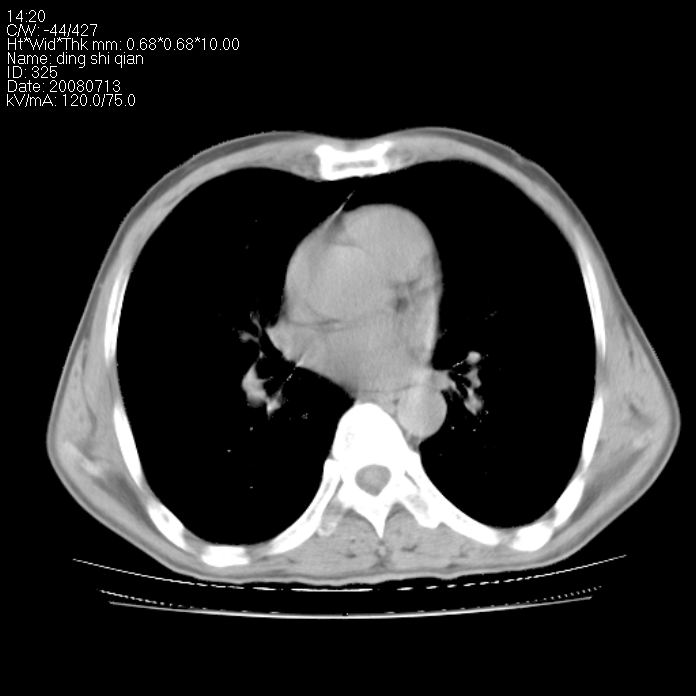

标题: CT14654:男 50岁 近来胸痛 [打印本页]

标题: CT14654:男 50岁 近来胸痛

右侧上肺块状软组织影,浅分叶,边缘毛刺证,与胸膜粘连,考虑:周围性肺癌

考虑: 右肺上叶周围型肺癌可能性大.